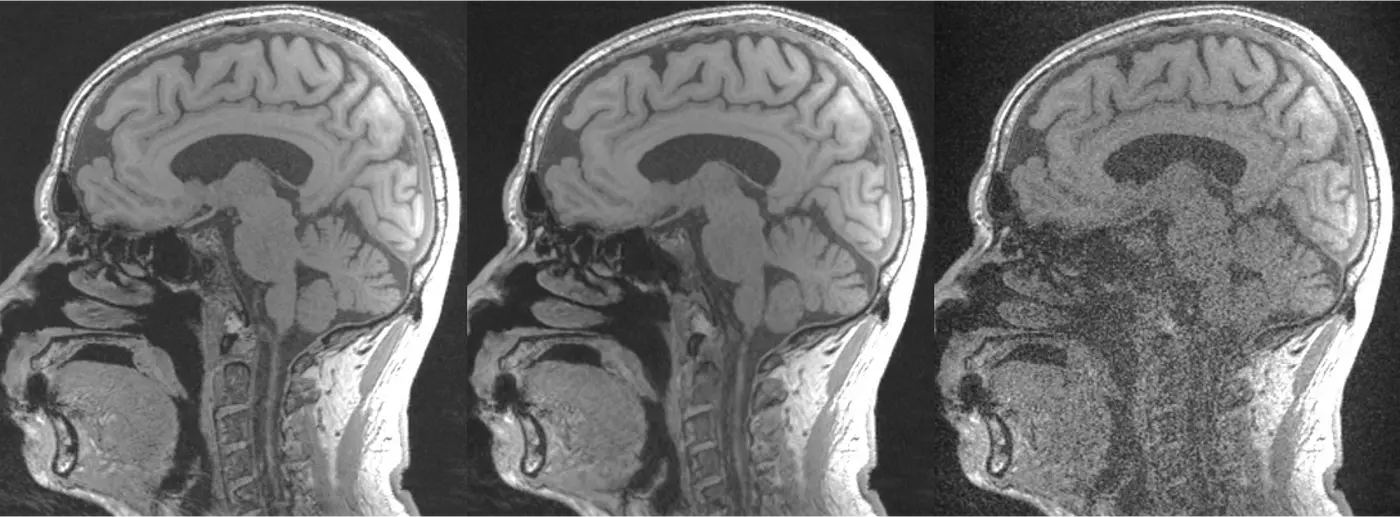

In 2019, Facebook AI Research (FAIR) and NYU Langone Health hosted the inaugural fastMRI Challenge↗ to make MRI scans up to 10X faster with AI. As part of the competition, NYU Langone Health released fully anonymized raw data and image datasets of 17K+ MRIs↗ to accelerate the clinical adoption of ML in MRI research broader machine learning community.

MRI reconstruction is both a GPU- and data-intensive task. The winning model of the 2020 fastMRI Challenge by AIRS Medical, for example, had 200M+ parameters trained on 4 NVIDIA V100s for 7 days. SNU wanted to scale that 150X — an environment in which 150+ teams could each train and optimize their own models.

The easy access to the school’s ML infrastructure, together with VESSL’s guided workflows, has lowered the barrier to experiment with SOTA models — helping students even without CS backgrounds to try out AI-enhanced research and applications rapidly. This makes it possible for the researchers to explore interdisciplinary possibilities that simply weren’t feasible before like the use of AI in MRI scans.